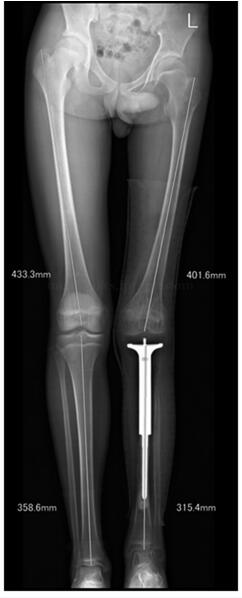

图47‐7 术后5年双下肢全长片示左胫骨较右胫骨短缩4﹒4cm,左股骨较 右股骨短缩约3.1cm

:患者术后未见明显并发症。目前患者术后5年,未发现局部复发及远隔转移。患者跛行步态。左膝关节主动活动度(伸直至屈曲):0~90°。下肢长度测量显示左胫骨较右胫骨短缩4.4cm,左股骨较右股骨短缩约3.1cm(图47‐7)。X 线显示假体未见明显松动,膝关节无脱位(图47‐8~图47‐10)。患者站立时由骨盆及脊柱倾斜来调整肢体长度(图47‐11)。